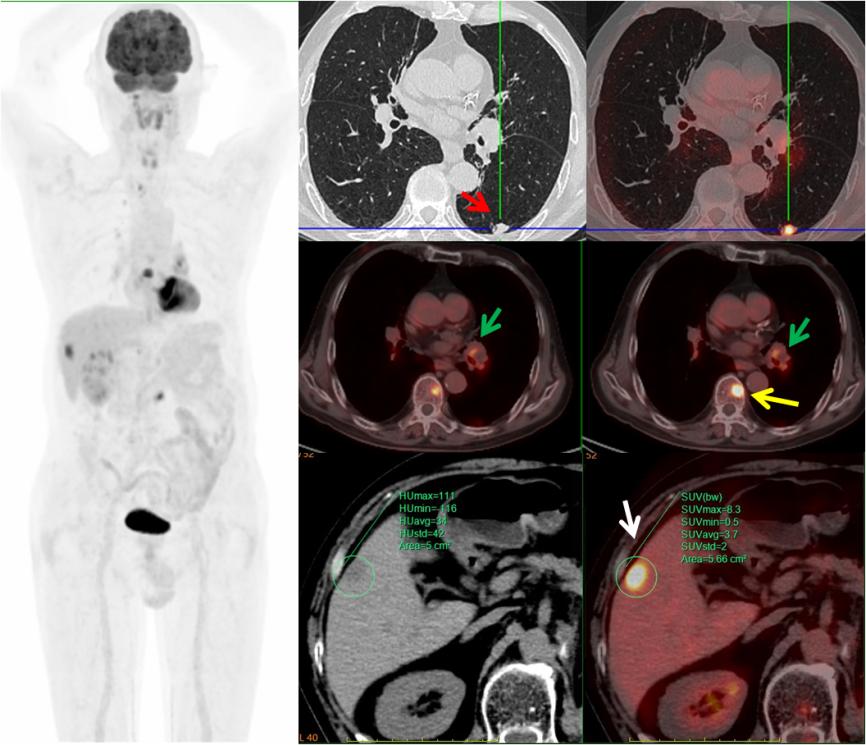

病例3,中年男性,左腎癌術(shù)后三個月,PET/CT示左肺下葉(紅箭)、左肺門淋巴結(jié)(綠箭)、肝臟(白箭)、多發(fā)椎體(黃箭)高代謝灶,考慮左肺下葉原發(fā)MT可能,病理證實(shí)為小細(xì)胞神經(jīng)內(nèi)分泌癌。